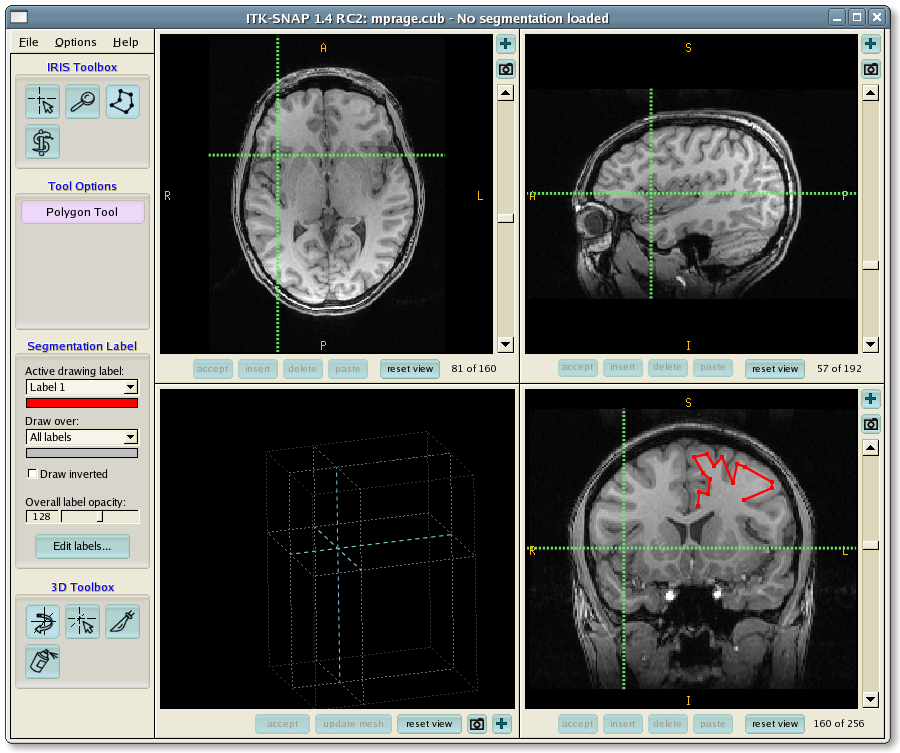

Лазерная камера для печати медицинских изображений на пленке стандарт dicom